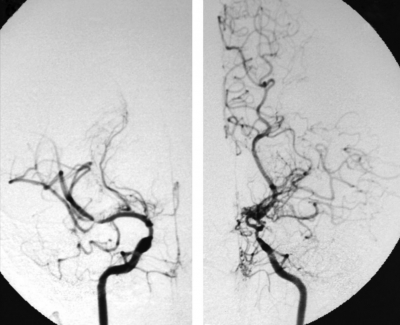

入院時の頭部 CT及び脳血管造影像を別に示す。